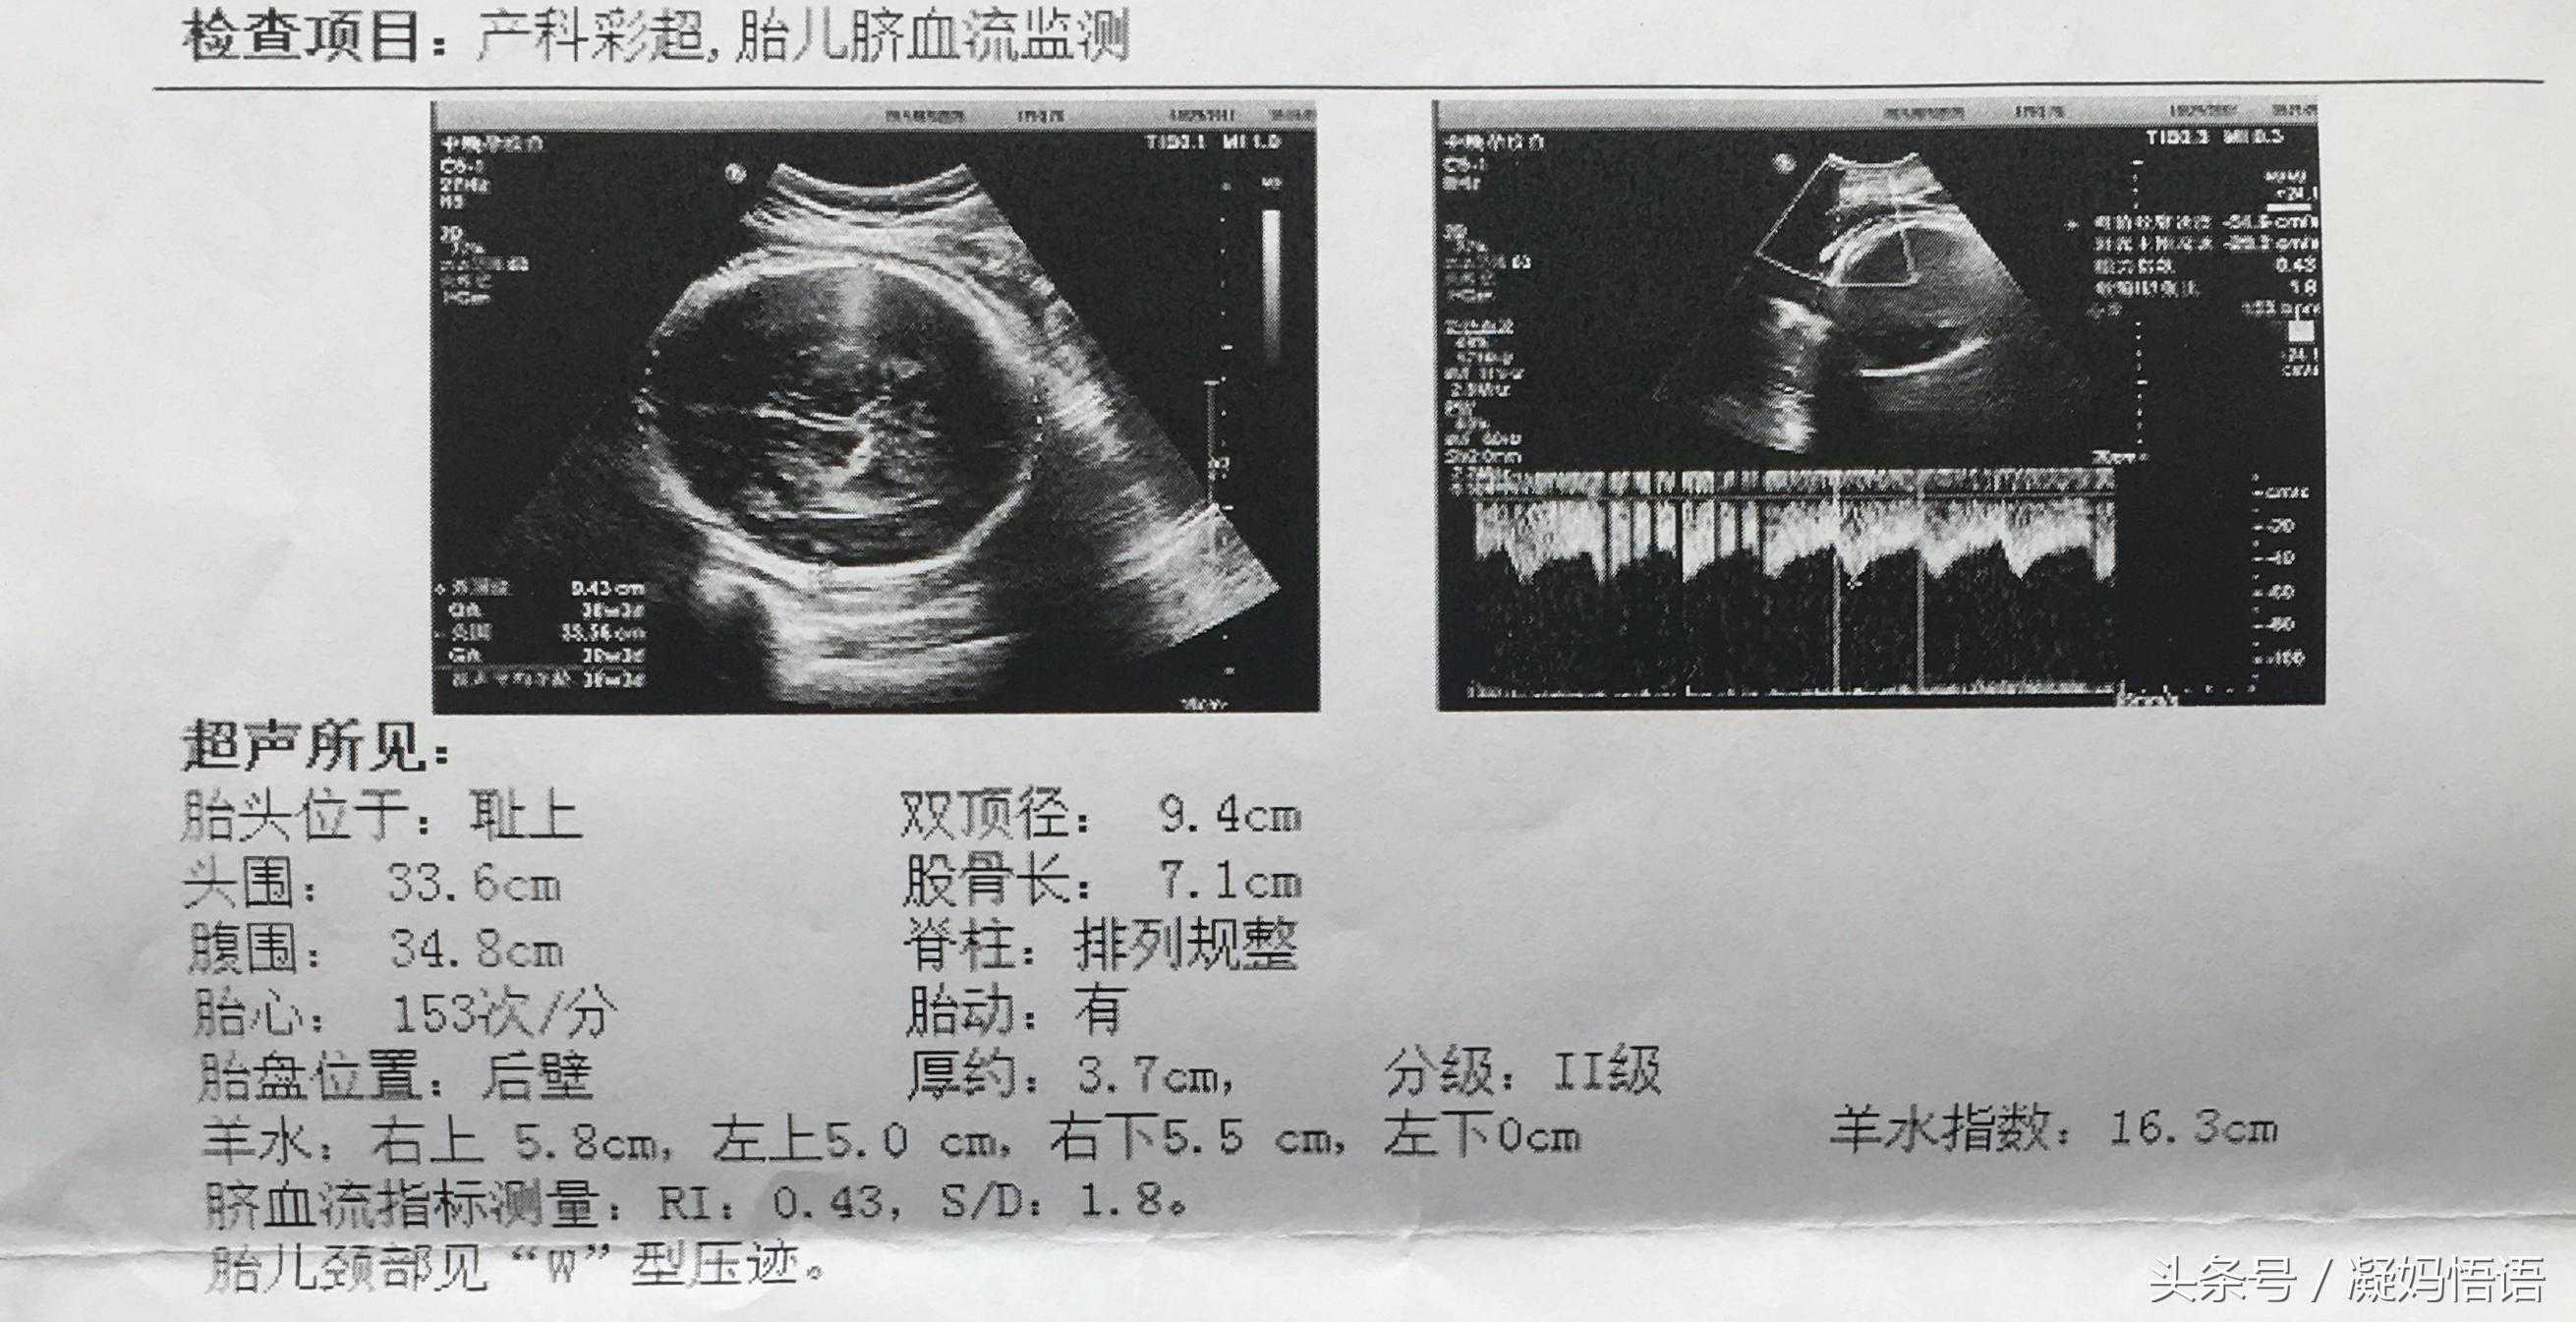

六、第六次彩超是在第38周,生之前的最后确认,加了胎儿脐血流监测。

胎心率是153次,大于140次,证明胎心率多少不是判断男女的标准。

双顶径是9.4cm,股骨长是7.1cm,9.4-7.1=2.3,大于2,这样判断是男孩貌似是准的。

有文章说右上角有个M,代表male,也就是男孩的意思,果真是对的。